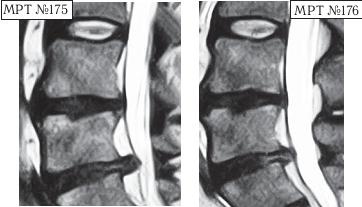

Вот ещё одни снимки МРТ другого пациента, которые наглядно демонстрируют процесс ретрузии грыжи диска.

На МРТ № 175 наблюдается состояние поясничного отдела позвоночника: компенсированная протрузия, грыжа Шморля в сегменте LIV-LV, спондилёз, гипертрофия задней и передней продольных связок, грыжа межпозвонкового диска сегменте LV—SI, стеноз спинномозгового канала.